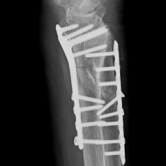

Röntgenbilder